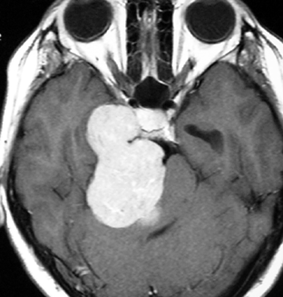

典型的な髄膜腫

この髄膜腫は中程度の大きさのものです。円蓋部髄膜種という最も多い最も手術の簡単なタイプです。麻痺や失語症やてんかんなどの症状はありません。とても美しくて若い女性の髄膜腫でしたが,子供に遺伝はしませんし,癌などと違ってタバコなどこれといった原因がなくて発生するものです。

最も見やすいのが,ガドリニウム造影剤を注射して撮影するものです。一般的に髄膜腫は造影剤で白く映し出されます。この腫瘍は左脳側にあります。MRIの軸面という輪切りの写真では左右が逆になりますから注意してください。脳を下から見た図になっています。MRIはいろいろな方向から腫瘍を見ることができますが,右は冠状断という正面から見た図です。よく見ると腫瘍の上と下のはじっこに線状に糸を引いたように造影される部分があります。これをテールサイン(しっぽのサイン)といいます。腫瘍が硬膜に沿って延びている可能性があることを示しています。